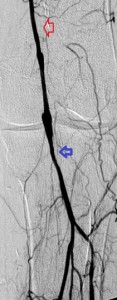

Key to images:

Bottom panel: Post intervention run-off arteriogram of the left lower extremity showing, from left to right, the proximal and distal segments of the re-opened left femoro-popliteal bypass (red arrows on images 1, 2, and 3). Contrast the full-column opacification of the below-knee left popliteal artery, arrowed blue on the 3rd image, and the enhanced visibility of the three-vessel subpopliteal domain to their vestigial appearances on the pre-intervention images, when they were poorly fed through collaterals.